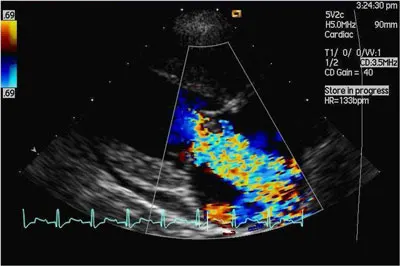

_Definitive Diagnosis_Echocardiography• Definitive diagnosis is made by identifying a distorted mitral valve and evidence of valvular insufficiency (in the absence of other cardiac disease); this can be achieved using echocardiography and Doppler echocardiography (Figure 1), respectively.• Clients may decide not to pursue Doppler echocardiography, particularly if their pets are not showing outward signs.• If the course of CVD in a small-breed dog is typical, many times a clinical diagnosis is made without definitive confirmation; however, if clients pursue optimal management, including definitive confirmation, Doppler echocardiography should be recommended to ensure an accurate diagnosis.

Figure 1: Color Doppler echocardiographic image (obtained from right side of the thorax) of a patient with marked mitral regurgitation: The heart is seen in long axis with the left ventricle displayed on the left side of the image and left atrium to the right. Mitral regurgitation is indicated by presence of a large, vividly colored jet of blood regurgitating from the left ventricle into the left atrium during ventricular systole.